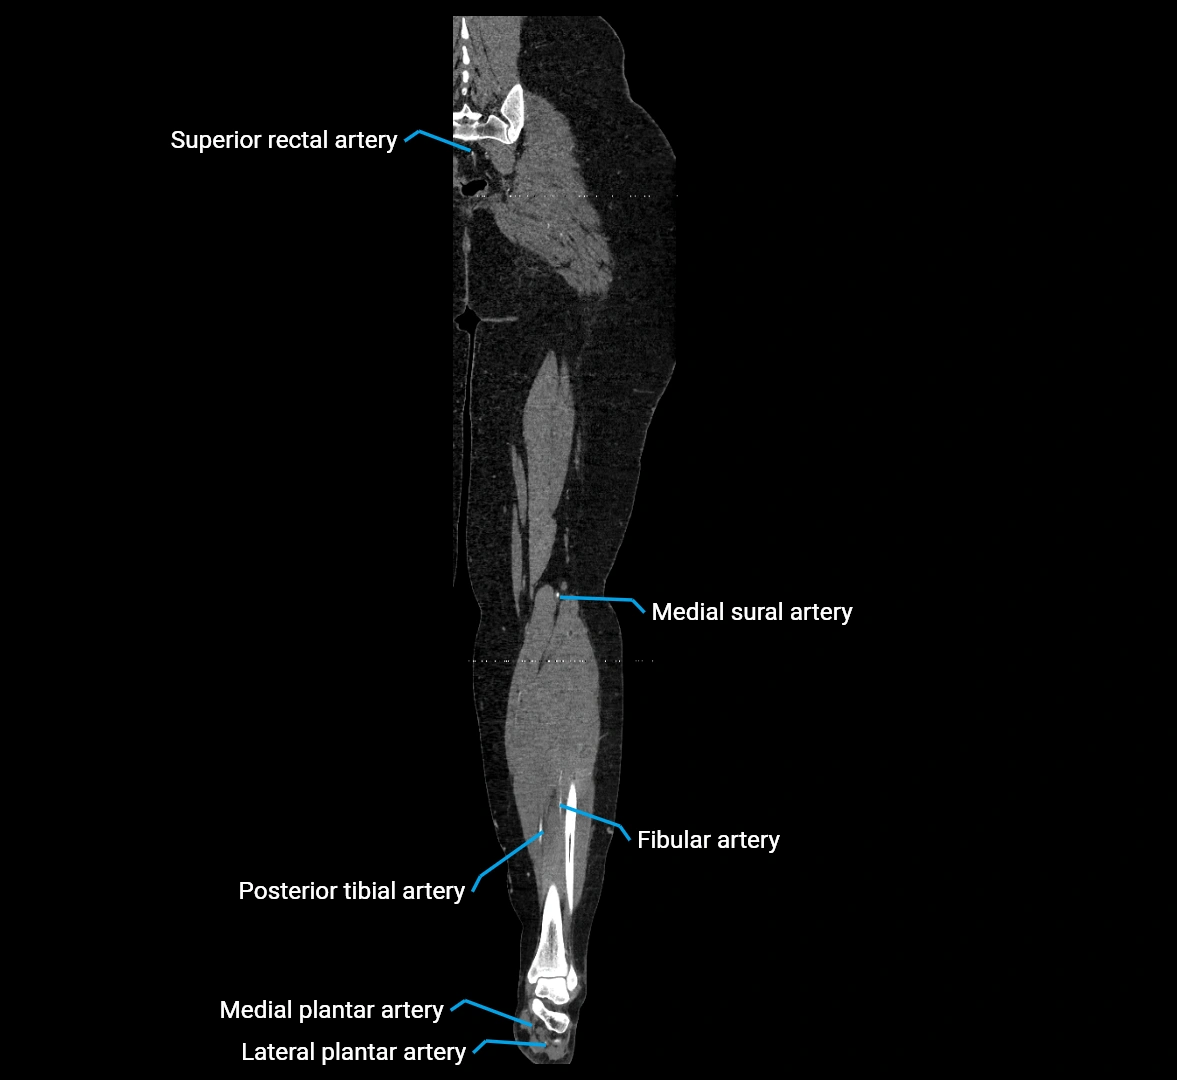

Contrast-enhanced CT (CTA):

• Gold standard for abdominal aortic imaging

• Provides excellent detail of lumen, wall, aneurysm, thrombus, and branch vessels

• Multiplanar and 3D reconstructions help in aneurysm measurement, stent graft planning, and dissection evaluation

• Detects acute rupture, traumatic injury, or occlusion with high sensitivity